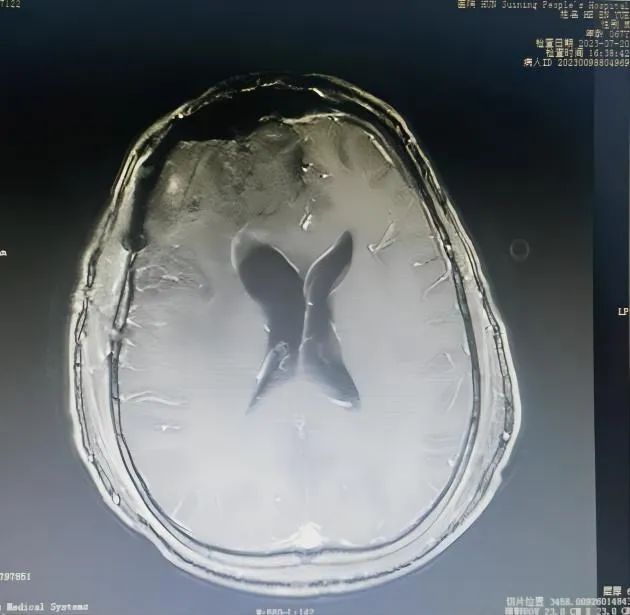

术前VS术后

术前VS术后 在廖新斌博士和黄敏主任的带领下,神经外科团队认真讨论并充分做好术前准备,如期为贺大爷实施了“前颅窝底复发肿瘤”切除术。手术效果及术后恢复良好,贺大爷于8月3日康复出院,并对科室团队的专业技术和卓越服务竖起了大拇指,其家属也送来锦旗表示感谢。